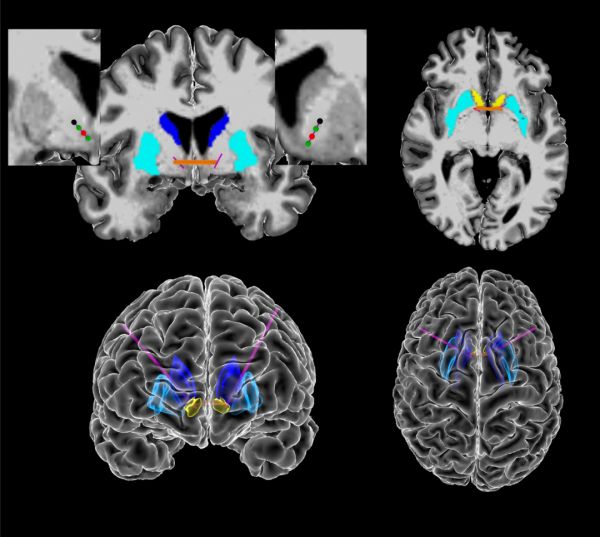

这个研究团队来自美国布朗大学脑科学研究所,David A. Borton 教授带领的研究团队通过对 5 名重度强迫症患者进行长期脑电监测,经过长期的收集研究与观察,利用人工智能对患者生活中的强迫行为进行分析,评估患者各种微妙的情绪变化,并与脑电波活动相匹配。除了脑电波信号,研究人员还收集了一套强迫症患者行为的生物标志物,包括面部表情和身体运动。通过人工智能,他们发现这些行为和特征与大脑内部信号变化密切相关。

并且,研究人员也用试验证明了,当患者出现这些强迫症状,依据AI给出的深部脑刺激位置,可以显著地改善患者的强迫症状。研究人员也在不断地精进深部脑刺激的系统,向自动化刺激的方向前行。

什么意思呢?就是在患者出现强迫症信号的时候,系统可自动捕捉并及时利用深部脑刺激进行针对性缓解,依据患者症状强度,自动调节刺激强度。目前研究人员计划进一步招募更多患者进行试验,以捕捉更多的强迫症脑电信号标志,丰富自动化深部脑刺激系统的功能。目前研究人员正在开发自动化深部脑刺激系统。